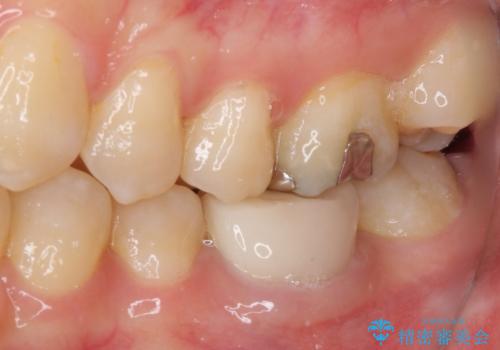

- 奥歯の形が気に入らないとのことで来院された患者様です。

形の変更を希望して、即日装着可能な歯科医院にて治療をしたそうですが、思い通りの形にできなかったとのことでした。

修正可能なように、従来通り技工所に発注して製作するオールセラミッククラウンにて補綴することとしました。